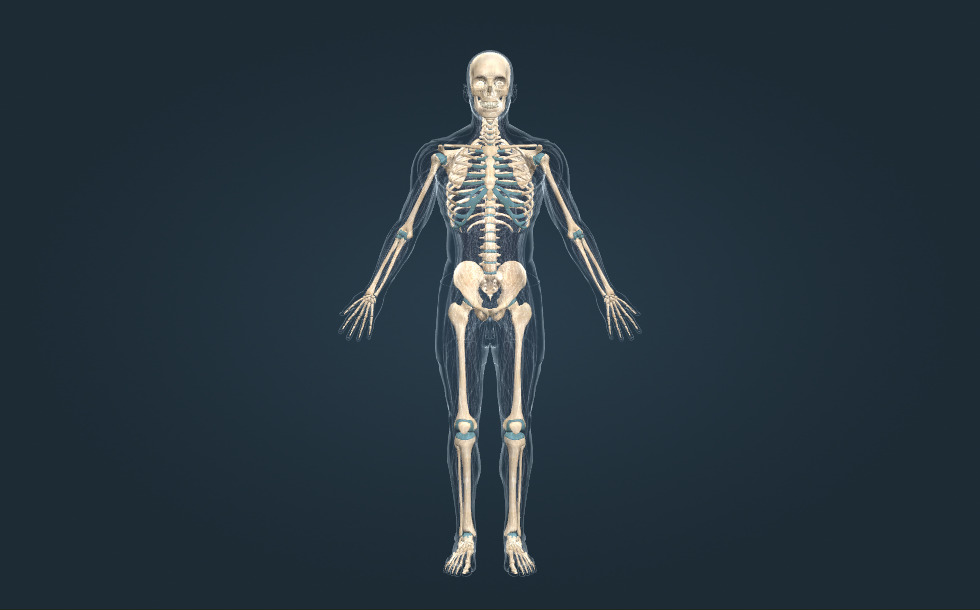

Σκελετός

- κρανίο - Περιέχει τον εγκέφαλο.

- σπονδυλική στήλη - Περιέχει το νωτιαίο μυελό.

- λεκάνη

- οστά των άνω άκρων

- οστά των κάτω άκρων

- στήθος

Ο σκελετός ενός ενήλικα ανθρώπου αποτελείται από 206 οστά. Τα οστά είναι άκαμπτα και ταυτόχρονα ευέλικτα για να κρατάνε μεγάλο βάρος. Ο μεταβολισμός των οστών είναι αργός, έτσι τα οστά αναρρώνουν αργά. Ένα σπασμένο οστό χρειάζεται τουλάχιστον 6 εβδομάδες για να συγκολληθεί. Η πρόσληψη της κατάλληλης ποσότητας ασβεστίου ημερησίως, 1500 mg για τους εφήβους, είναι απαραίτητη για την αποφυγή της οστεοπόρωσης.

Ο σκελετός ενός ενήλικα ανθρώπου αποτελείται από 206 οστά. Τα οστά είναι άκαμπτα και ταυτόχρονα ευέλικτα για να κρατάνε μεγάλο βάρος. Ο μεταβολισμός των οστών είναι αργός, έτσι τα οστά αναρρώνουν αργά. Ένα σπασμένο οστό χρειάζεται τουλάχιστον 6 εβδομάδες για να συγκολληθεί. Η πρόσληψη της κατάλληλης ποσότητας ασβεστίου ημερησίως, 1500 mg για τους εφήβους, είναι απαραίτητη για την αποφυγή της οστεοπόρωσης.